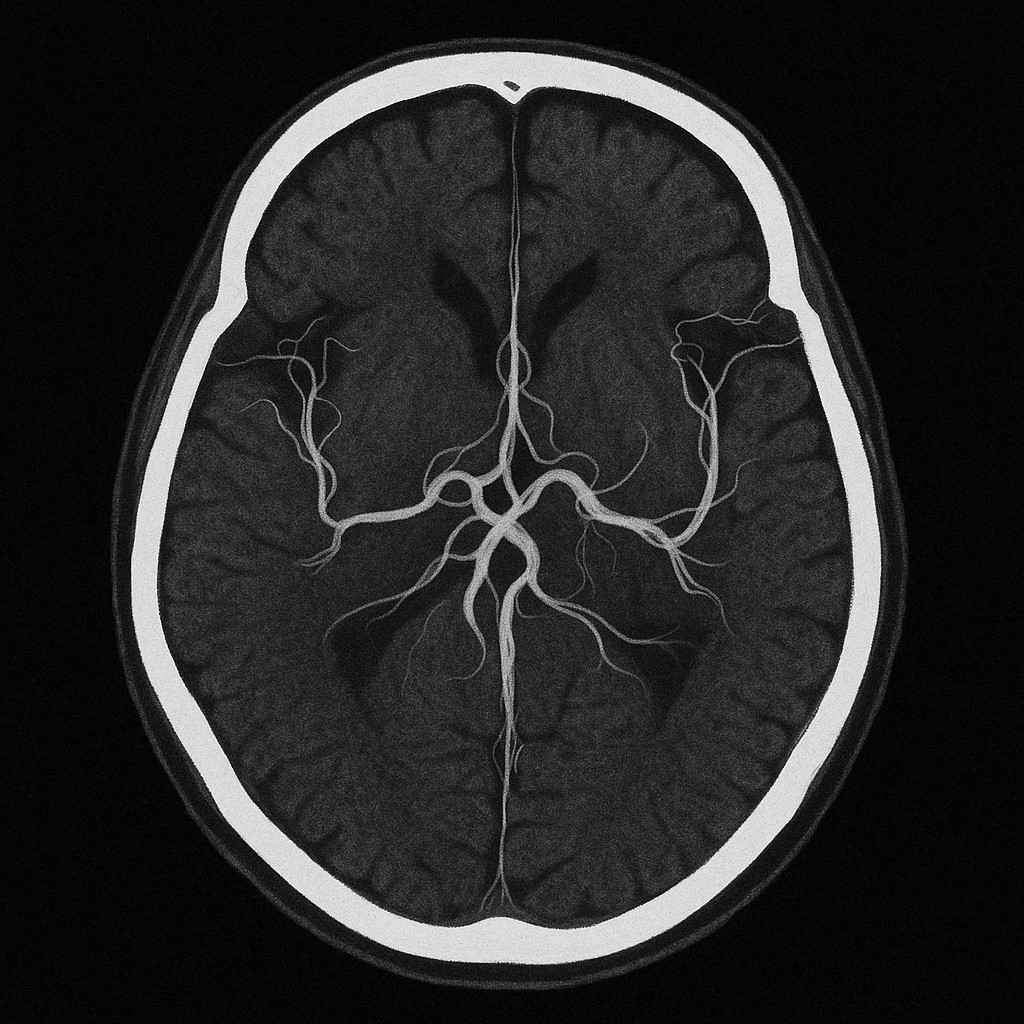

뇌졸중은 뇌에 혈류 공급이 차단되거나 혈관이 터지면서 뇌조직이 손상되는 병이에요. 크게 **허혈성(뇌경색)**과 **출혈성(뇌출혈)**으로 나뉘며, 발병 원인은 고혈압, 당뇨, 고지혈증, 심장질환 등이 있어요.